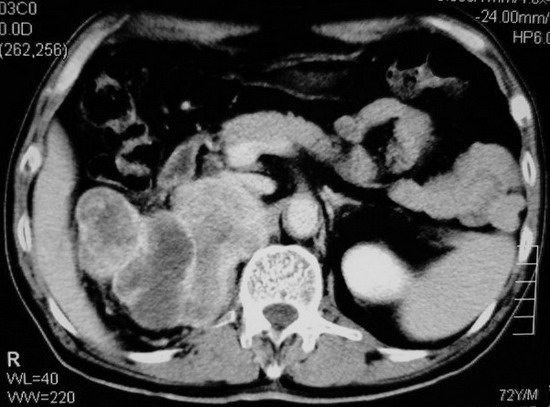

以下是引用杀毒软件在2008-11-17 19:15:00的发言:[br]考虑------右肾癌合并肾静脉---同侧肾上腺受侵可能性大

以下是引用zjzjr在2008-11-17 20:45:00的发言:[br]考虑------右肾癌合并肾静脉---同侧肾上腺受侵可能性大及腹膜后淋巴结转移.